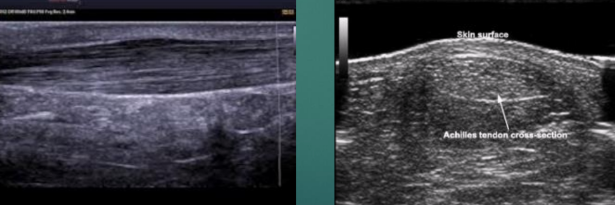

US appearance of tendons

LAX

Linear band of hyperechoic strands and fibrillar pattern, interspersed with relatively hypoechoic connective tissue

SAX

“Whisk-broom” appearance

Hyperechoic foci throughout tendon distribution interspersed by hypoechoic connective tissue

Must maintain uniform thickness throughout except at site of insertion (might broaden)

Normal US appearance of Achilles tendon